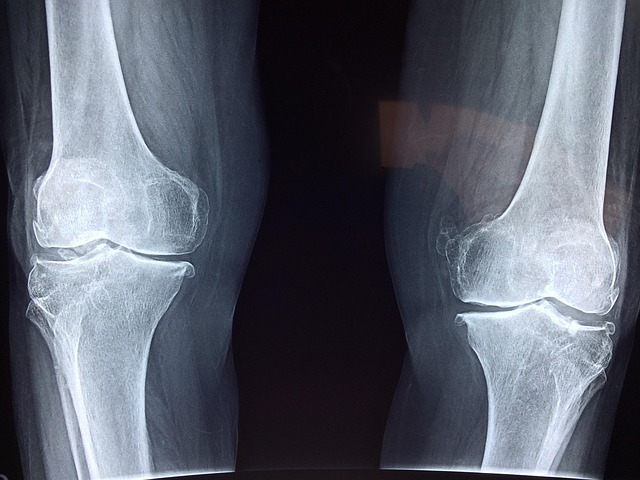

칼슘 & 비타민 D

✔ 뼈와 관절을 튼튼하게 유지하는 필수 영양소

✔ 골다공증 예방 및 뼈 건강 유지

우유 & 멸치

✔ 칼슘과 비타민D가 풍부해 뼈와 연골 강화

✔ 골다공증 예방